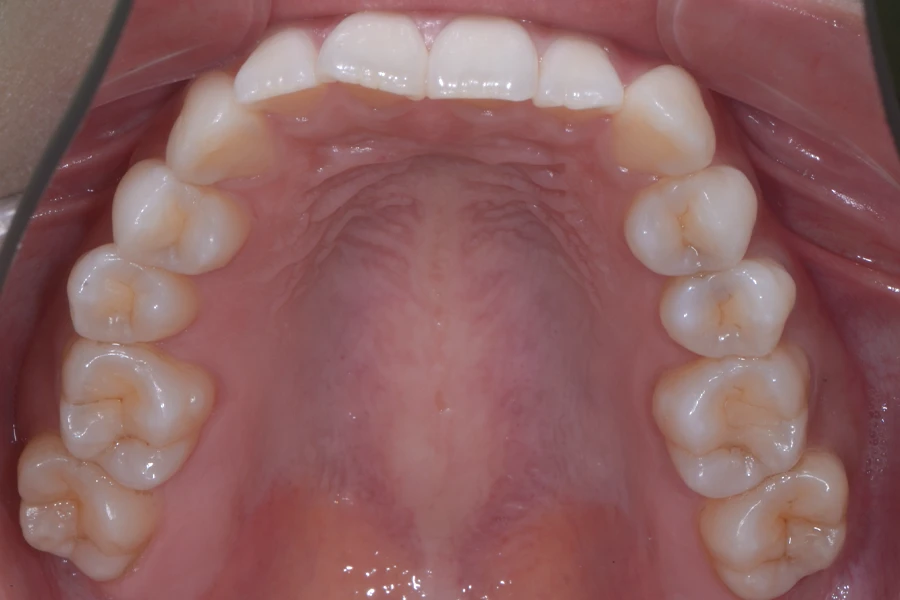

治療前

主訴 結婚式までに前歯を綺麗に整えたい

期間 10か月

費用 40万円(別途調整料)

デンタルローン80回 ¥5,800/月

治療内容 上下顎ラビアル矯正(表側矯正)

治療に伴うリスク 後戻り